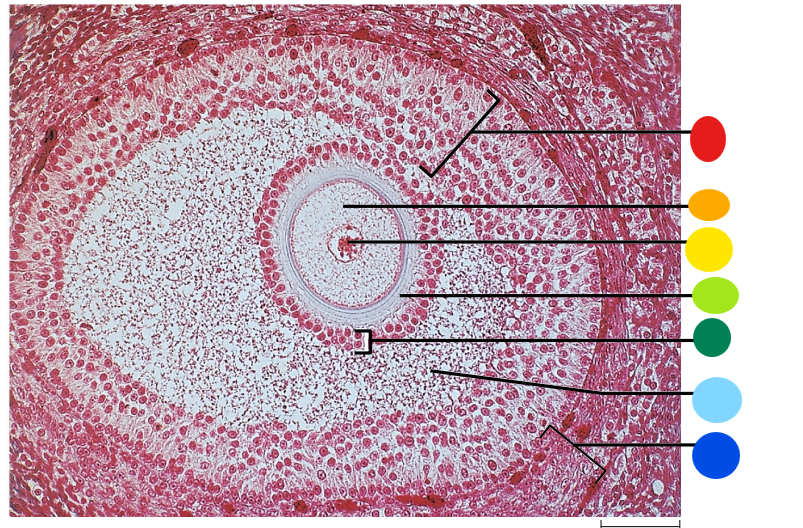

red

granulosa cells

orange

primary or secondary oocyte

yellow

oocyte nucleus

light green

zona pellucida

dark green

cumulus oophorus

light blue

antrum

dark blue

thecal cells

what is this

tertiary follicle